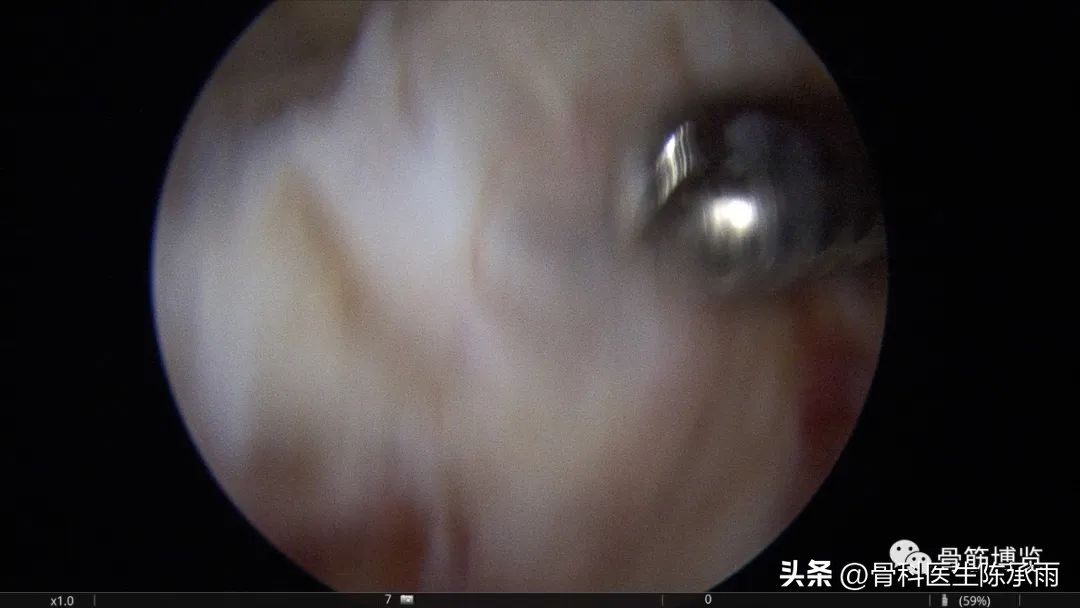

本例为内侧半月板前角巨大囊肿,关节镜下行半月板囊肿引流减压+囊肿前壁及囊壁滑膜切除+半月板缝合术。术中切除全部囊壁内滑膜及前壁及大部分后壁,保留部分后壁组织,以保证半月板前角缝合可靠及稳定。

术中情况

半月板囊肿分型决定了治疗方法的选择,对于前两种半月板囊肿因伴有半月板的损伤治疗方法相对复杂,半月板囊肿合并的半月板损伤多为水平撕裂或复杂撕裂,而且病史较长,因此需严格掌握缝合手术的指证。手术操作要点:采用常规的髌下内侧和髌下外侧入路,探查关节内囊肿和半月板撕裂的大致范围;使用刨刀细致地将囊肿切除,尽量彻底切除囊壁,充分敞开囊腔,避免囊肿复发,囊肿内可有分房或分隔现象,注意避免遗漏。注意在手术时尽量保留冠状韧带,避免冠状韧带的广泛缺损;进一步仔细探查损伤的半月板组织,明确撕裂的范围在红﹣红区或红﹣白区,对于超出上述范围的损伤或半月板的复杂撕裂及水平撕裂,放弃缝合手术,如条件许可时可在切除部分半月板(如切除水平撕裂的两片中不稳定的一片)的基础上进行缝合手术。然后以刨刀或磨钻小心修整损伤的半月板组织,使对合面整齐并显露新鲜组织;髌下外侧人路置人工作套管,附加经髌韧带的正中入路,严格解剖复位。经正中人路置人探针,固定半月板撕裂部位,使用肩袖缝合器经髌下外侧入路工作套管,缝合器尖端首先由半月板前缘和冠状韧带的交界处穿人半月板下表面后,越过半月板裂隙,在对侧由下到上穿出半月板上表面,经工作套管将线导出,体外打 Duncan 结,推线器将线结推人至半月板前缘处拉紧,再打两个套结,剪断缝线。两缝线之间间距8 mm 。滑膜囊肿的手术操作相对简单:镜下切除囊肿后,将半月板与冠状韧带之间的缺损区缝合。